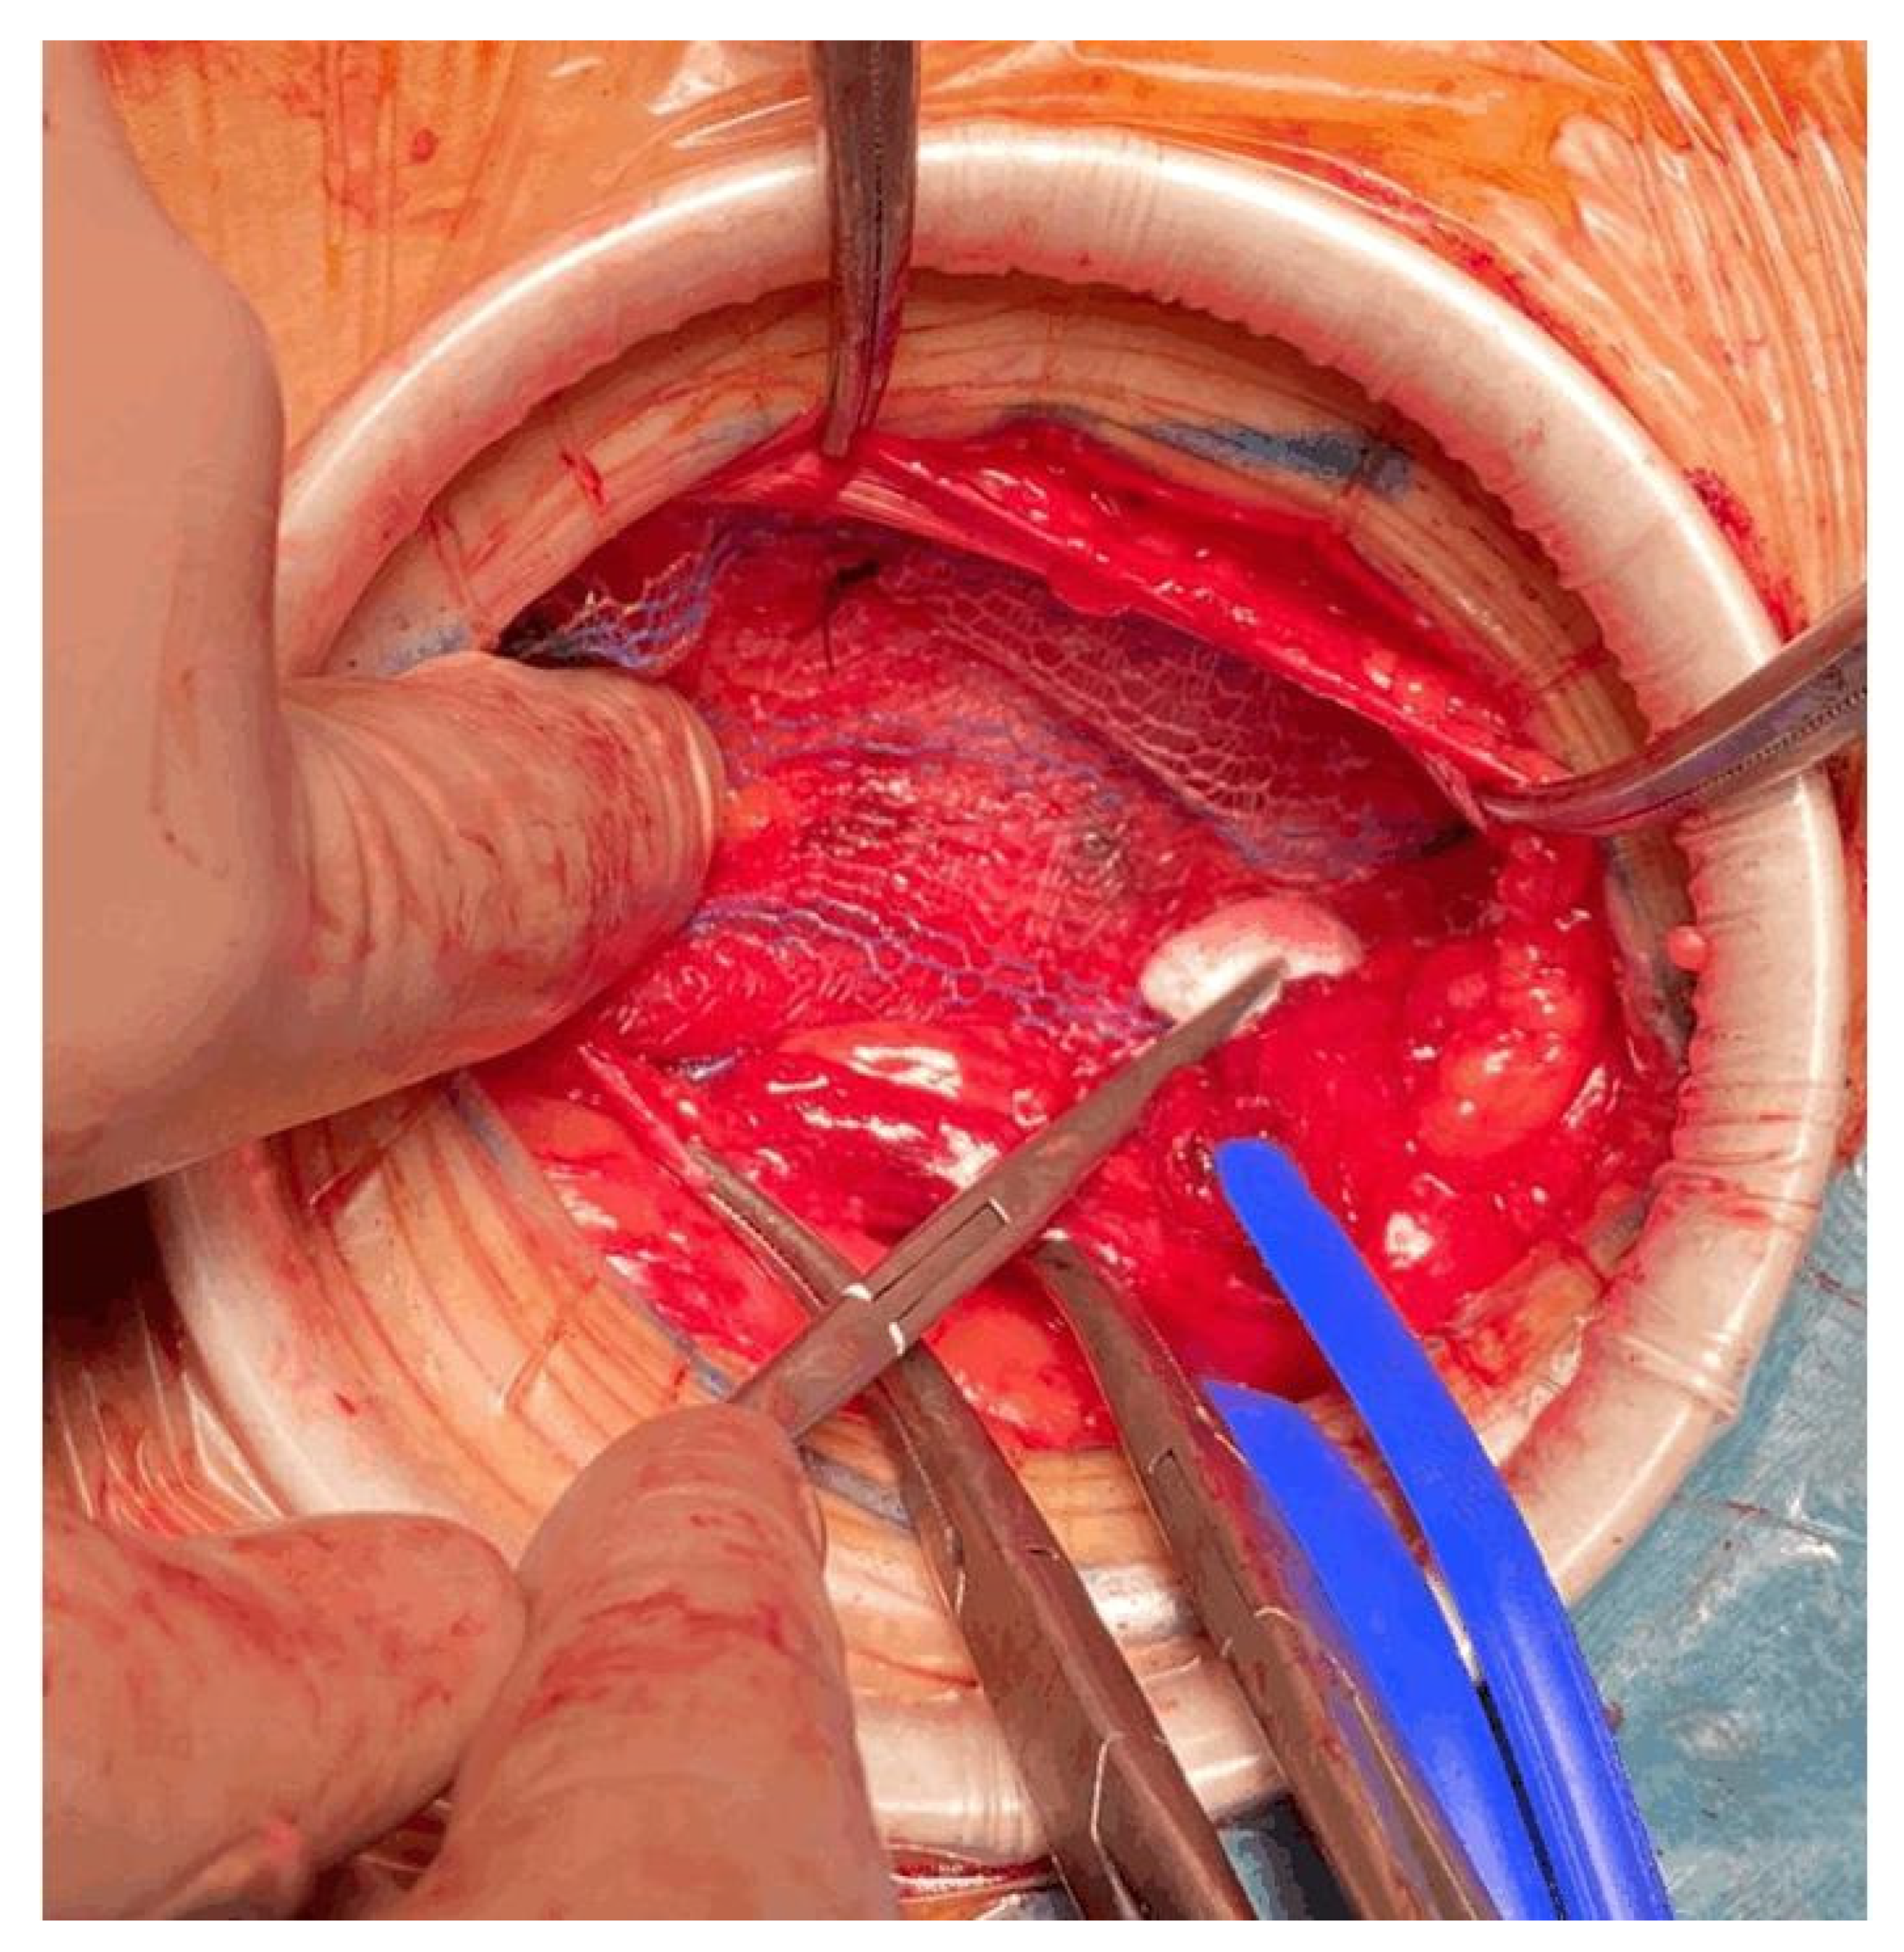

Anesthesia alone may not be adequate to control pain during hernia repair. One of the main causes of pain is traction. Traditionally, adequate surgical exposure has been accomplished with the aid of self-retaining retractors or by extending the incision length. Self-retaining retractors can lead to potential complications, including local tissue ischemia and pain.

To reduce traction during hernia repair, we used the Alexis™ S wound retractor. It provides 360 degrees of atraumatic circumferential retraction. The wound protector is placed after the incision of Scarpa’s fascia, exposing the aponeurosis of the abdominal external oblique muscle. With their index finger, the surgeon creates space towards the testicle, and then the surgeon places the Alexis™ S wound retractor, as seen in Figure 8 and Figure 9.

Figure 8.

The wound protector provides a significant increase in surgical exposure compared to self-retaining retractors. The wound protector reduces the depth of the operative site, and it is helpful in obese patients. The reduction in traction improves postoperative pain due to the lower compressive force.

Several studies have reported the decreased rates of SSI even in clean wounds such as elective inguinal hernia repair [18,19,20].